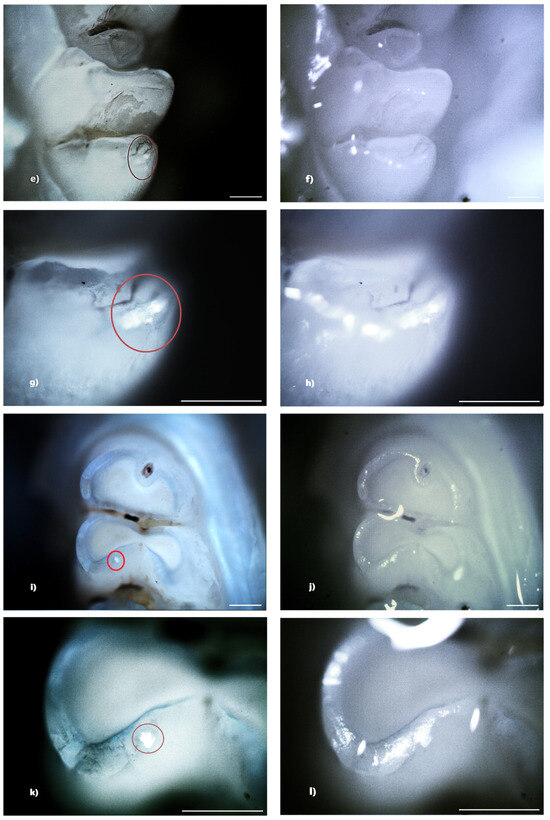

Figure 6. Hypoplasia on the palatal surface of a molar (a—PLM image, cross polarizers, 4× objective; b—BFM image, 4× objective) and on the distal surface of some molars (e,g—PLM, cross polarizers, 4× objective; f,h—BFM image, 4× objective); demineralization on the occlusal surface of a molar (c—PLM image, cross polarizers, 4× objective; d—BFM image, 4× objective) and on the buccal surface of a molar (e—PLM image, cross polarizers, 4× objective; f—BFM image, 4× objective). Scale bar represents 500 μm.

In the group receiving double-dose amoxicillin (100 mg/kg), 13 rats (86.67%) showed at least one clinical form of DDE. Of these, seven rats were affected by hypoplasia and five rats were affected by demineralization. One rat showed both clinical forms of DDE. Within this group, out of a total number of 240 teeth, 43 teeth (17.92%) had at least one lesion. Among them, 13 teeth (30.23%) were incisors and 30 teeth (69.77%) were molars, and as a clinical form of DDE, 25 teeth (58.14%) showed hypoplasia (5 incisors and 20 molars) and 18 teeth (41.86%) showed demineralization (8 incisors and 10 molars). Among the 43 teeth with DDE, 3 teeth showed DDE on two surfaces, resulting in 46 affected tooth surfaces (Figure 6).